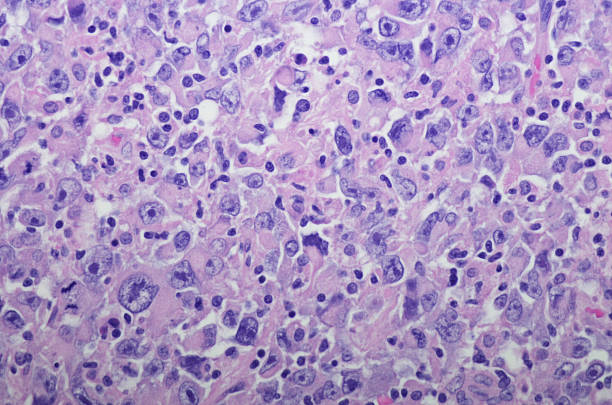

현미경적 혈뇨는 신장암의 초기 증상 중 하나로 나타날 수 있습니다. 이는 소변에서 피가 혼합되어 나오는 것을 의미합니다. 때로는 눈에 띄지 않을 수 있지만 검사를 통해 혈뇨가 확인될 수 있습니다. 특히 50세 이상의 연령대에서 현미경적 혈뇨가 나타날 경우, 초음파 검사나 CT 검사와 같은 특수 검사를 받아야 합니다. 이를 통해 신장암의 가능성을 조기에 확인할 수 있습니다.

3. 물혹

물혹은 신장에서 발생하는 낭종으로, 별다른 증상이 없을 수 있습니다. 하지만 이러한 낭종이 발견될 경우, 신장암으로 진행할 가능성이 있는 경우도 있습니다. 따라서 물혹이 있는 경우에도 정기적인 검사를 통해 신장의 건강 상태를 모니터링하고, 필요한 경우 추가 검사를 받는 것이 중요합니다.